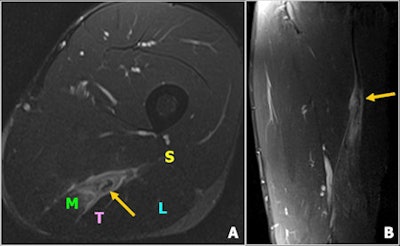

"Fluid-sensitive MR sequences are suitable for detecting edematous changes in the muscles," noted lead author Dr. Daichi Hayashi, PhD, a research assistant professor of radiology at Boston University School of Medicine in the U.S. "T1-weighted sequences are used to differentiate between hemorrhage/hematoma and edema."

Over recent years, MRI has become a valuable tool for evaluation of traumatic muscle injuries, especially among football players, dancers, track and field athletes, and other competitive athletes. Under normal circumstances, images from only the affected leg are acquired using a surface coil, but the appropriate coil should be selected to obtain the desired field-of-view. Imaging of the contralateral leg is performed in exceptional cases only (e.g., bilateral injury).